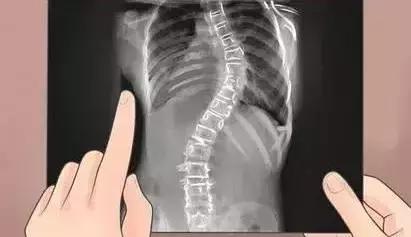

西安交通大学第一附属医院脊柱外科主任陶惠人表示,脊柱侧弯无疑是一个需要家长进行高度警惕和重视的疾病。脊柱侧弯多以驼背、侧弯为主,目前我国发病人群约为200万人左右。孩子在成长过程中,一旦出现驼背、胸椎后凸明显、后背有包块、隆起和异常的毛发、双下肢不等长等情况时,都应及时到医院检查和治疗。

发现脊柱侧弯早期征兆应立即到医院找专科医生诊看。专科医生会通过孩子生长发育的情况、脊柱侧弯的度数,以及是否经过其他的锻炼和治疗,来判断脊柱侧弯是否会进一步加重,并为患者安排相应的治疗方案。

正常脊椎从正面看是直的,从侧面看有三条曲线,颈椎略向前,胸椎略向后,腰椎略向前,整个脊柱类似于一个完美的S曲线。在脊柱弯曲的情况下,从前后来看,脊柱是偏向一侧的, 大多数情况可根据保守治疗进行控制和治疗。症状严重者可通过手术治疗。